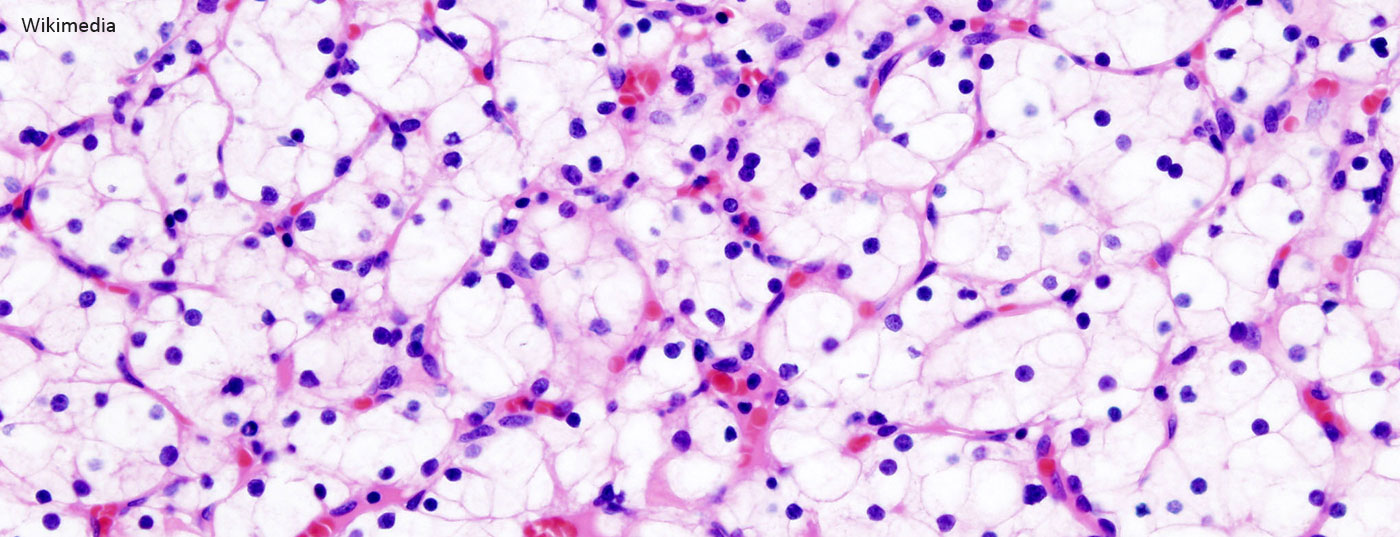

nierenkrebs_nierenkarzinom_wikimedia-free

• Metastasiertes Nierenzellkarzinom (mRCC)

Individuelles Therapiemanagement verbessert den Behandlungserfolg

Das immer bessere Verständnis der pathogenetischen Zusammenhänge des Nierenzellkarzinoms hat zur Entwicklung neuer Medikamente beigetragen. Diese greifen spezifisch in die VEGF, PDGF und mTOR-Signalwege ein. In den letzten Jahren wurden zudem Therapien entwickelt, die das Immunsystem auf die Tumorbekämpfung ausrichten. Wo stehen wir beim mRCC heute? Was sagen die aktuellen Guidelines?